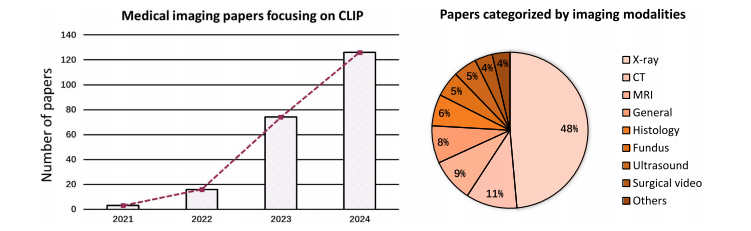

尽管在过去十年中视觉智能领域取得了重大进展(何恺明等人,2016;塔尔瓦宁和瓦尔波拉,2017;多索维茨基等人,2020;刘等人,2021,2022b),但视觉模型通常仅在视觉模态的注释和任务上进行训练(龙内贝格尔等人,2015;何恺明等人,2017;伊森塞等人,2021;何恺明等人,2021)。尽管其中一些方法已经达到了人类水平的性能,但由于缺乏与人类认知的对齐,它们在分布外的性能仍远不能令人满意(彼得森等人,2019;巴特勒迪等人,2020;盖尔霍斯等人,2020;彼得斯和克里格斯克特,2021)。相比之下,文本监督的形式在语义上自然丰富,并且相应的语言模型,尤其是如今的大型语言模型(图夫龙等人,2023;熊等人,2023;张等人,2023a),通常包含大量的人类水平知识。因此,将文本监督整合到视觉任务中是很直观的想法。 受对比预训练的启发,拉德福德等人(2021)提出了对比语言 - 图像预训练(CLIP),它从文本监督中学习可解释的视觉表示。与大多数仅针对视觉的对比预训练方法(陈等人,2020a;卡龙等人,2021;兹邦塔尔等人,2021)不同,CLIP 同时利用了视觉和语言信息。具体来说,它将文本字幕视为图像的一种语言视角,并期望它与图像在本质上是一致的。因此,它在潜在空间中尽可能拉近成对的图像和文本表示。通过这种方式,图像 - 文本对通过 CLIP 的视觉和文本编码器进行对齐,从而大量的知识被编码在视觉编码器中。受益于图像 - 文本对齐,CLIP 从文本监督中学习了广泛的知识,并已被证明在许多领域都很有用,包括图像生成(温克等人,2022;拉梅什等人,2022;于等人,2022;龙巴赫等人,2022)、分割(李等人,2022a;饶等人,2022;罗等人,2023)、检测(班加拉特等人,2022;林和龚,2023)和分类(周等人,2022b,c;王等人,2023b)。 最近,CLIP 在医学成像领域也受到了越来越多的关注(埃斯拉米等人,2021;王等人,2022e;金等人,2024)。图 1 的左图展示了医学成像领域中与 CLIP 相关论文的增长趋势,从 2021 年下半年到 2023 年下半年呈现出数倍的增长,尤其是在 2023 年呈现出蓬勃发展的趋势。这可以归因于它能够使神经网络与人类认知对齐,满足了医疗保健领域人工智能对可解释性的需求(劳里岑等人,2020;乔亚和关,2020;谢等人,2021)。尽管先前的研究试图通过额外的专家级注释来提高可解释性,例如边界框(罗等人,2022;欧阳等人,2020;谷田等人,2023;米勒等人,2023)和分割掩码(梅塔等人,2018;周等人,2019),但收集这些注释既费力又耗时(拉希米等人,2021;王等人,2022b;曲等人,2023),这使得它们难以大规模应用。相反,在临床实践中由医学专业人员常规生成和收集的文本报告(黄等人,2021;王等人,2022a;谢等人,2023)以很少的额外成本提供了有价值的专家级知识,这使得 CLIP 成为一个更有前景的解决方案。 动机:尽管许多研究致力于为医学图像分析定制 CLIP,但这种定制带来了一些仍未解决的新挑战。为了鼓励和促进医学成像领域中基于 CLIP 的研究,对现有文献进行综述将是有益的。因此,我们广泛回顾了该领域 200 多种现有方法,以提供有见地的综述。 搜索策略:我们在包括谷歌学术、DBLP、arXiv 和 IEEE Xplore 等学术平台上进行搜索。利用“CLIP”、“图像 - 文本对齐”和“医学成像”等关键词,我们的初步探索涵盖了各种来源,如高影响力的期刊论文、会议/研讨会论文以及仍在评审中的预印本。我们排除了仅将 CLIP 用作基线方法的研究以及不专注于医学成像的研究。鉴于在稳定扩散(龙巴赫等人,2022)取得成功后,CLIP 文本编码器已成为扩散模型(卡泽鲁尼等人,2023)中的关键组件,我们也排除了主要关注扩散模型而非 CLIP 的论文。此外,手术视频和超声等成像模态通常以视频片段的形式呈现。因此,一些专注于这些模态的研究被错误检索到,即使它们没有使用与 CLIP 相关的技术。这些误检索的研究经过人工审查后被排除,而确实采用了 CLIP 的相关研究则被保留。应用这些选择标准后,我们确定了总共 224 篇用于本次综述的论文。按各自使用的成像模态分类的所选论文分布如图 1 的右图所示,其中基于 X 射线的研究占大多数。 分类方法:为了简化我们对医学成像领域中与 CLIP 相关工作的讨论,在本次综述中,我们将它们分为两类,即(1)改进的 CLIP 预训练和(2)由 CLIP 驱动的应用,如图 2 所示。第一类研究侧重于将 CLIP 的预训练范式从网络爬取的图像字幕对调整为医学图像及其相应的报告。第二类研究倾向于直接采用预训练的 CLIP 模型,以提高深度学习模型在各种临床任务中的可解释性和鲁棒性,例如胸部疾病诊断和多器官分割(蒂乌等人,2022;佩莱格里尼等人,2023;刘等人,2023g)。 相关综述:有一些与我们的综述范围相似的同期综述。 例如,什雷斯塔等人(2023)的一篇综述论文侧重于医学视觉语言预训练。他们的综述与我们的综述之间的区别在于:(1)他们主要探索各种视觉语言预训练架构,包括掩码预测(卡雷等人,2021)、对比(黄等人,2021)、匹配预测(穆恩等人,2022)和混合架构(王等人,2021a),对 CLIP 风格的对比预训练的关注较少;(2)他们主要关注大规模预训练,缺乏对临床任务的讨论。由于缺乏大规模的公共医学图像 - 文本数据集,他们的综述的影响可能有限。相比之下,我们的综述深入探讨了由 CLIP 驱动的应用,由于对数据的要求较低且对现实世界临床任务具有更多价值,这些应用在现实环境中更可行。此外,阿扎德等人(2023)探索了医学成像中的基础模型,他们的综述论文中也包括了 CLIP。与我们的综述论文的主要区别在于,他们主要涵盖仅视觉、仅语言和视觉 - 语言基础模型,而我们专门关注 CLIP,这是一种视觉 - 语言基础模型。此外,他们的综述也缺乏对临床应用的讨论,而我们对此进行了广泛的涵盖。因此,我们的综述(与上述两篇综述论文相比)将在技术和临床应用方面提供更有见地和更深入的综述。 贡献:总之,我们的贡献如下: - 据我们所知,本文是对医学成像中 CLIP 的首次综述,旨在为这个快速发展领域的潜在研究提供及时的总结和见解。 - 我们全面涵盖了现有研究,并提供了一个多层次的分类方法,以满足读者的不同需求。 - 此外,我们讨论了该领域的问题和开放性问题。我们还指出了新的趋势,并提出了进一步探索的未来方向。 论文结构:本文的其余部分组织如下。第 2 节提供了 CLIP 及其变体的初步知识。在第 3 节中,我们从关键挑战和相应解决方案的角度,对如何使 CLIP 适应医学成像领域进行了系统分析。第 4 节涵盖了预训练 CLIP 的各种临床应用,并将由 CLIP 驱动的方法与早期方法/解决方案进行了比较。第 6 节进一步讨论了现有局限性以及潜在的研究方向。我们最后在第 7 节中对本文进行总结。

Fig. 1. Left: Rapid increase in medical imaging papers focusing on CLIP. **Right:** Distribution of papers included in this survey, classified by different imaging modalities. Studiesleveraging CLIP for developing generalist medical AI are classified as ‘‘General’’. Imaging modalities rarely used, including placenta, dermoscopy, and electrocardiograms, aregrouped under ‘‘Others’’.

图1. 左侧:专注于对比语言-图像预训练模型(CLIP)的医学成像领域论文数量迅速增长。右侧:本综述所纳入论文按不同成像模态分类的分布情况。利用CLIP开发通用医学人工智能的研究被归类为“通用”类别。较少使用的成像模态,包括胎盘成像、皮肤镜检查以及心电图检查等,被归在“其他”类别下。